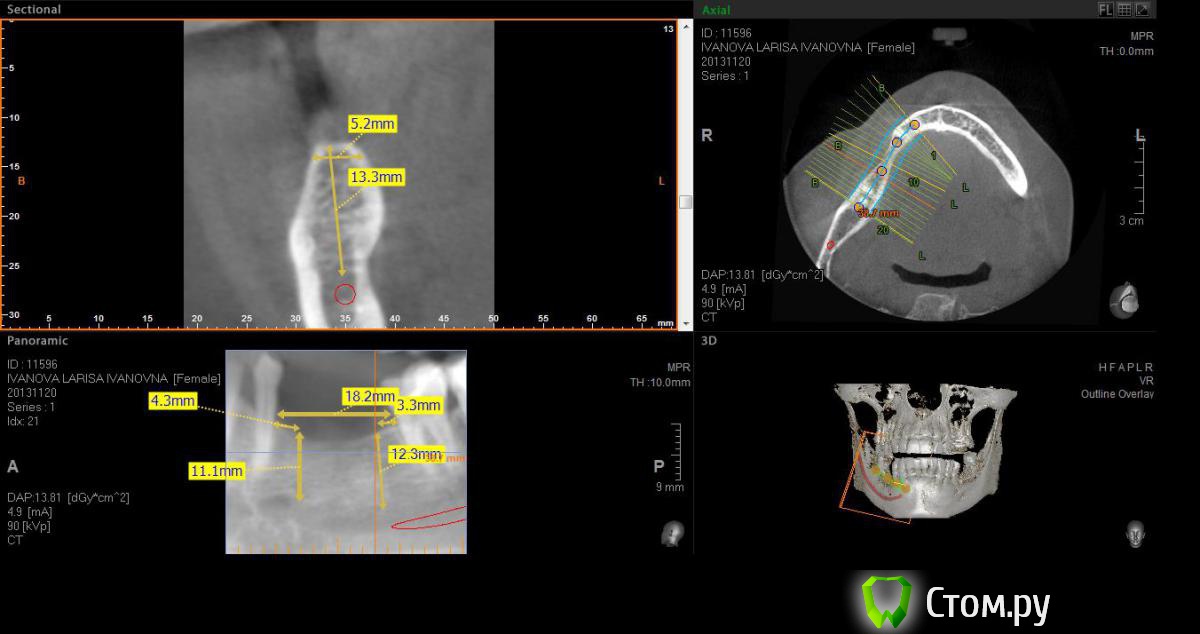

Neilrus Опубликовано 2 марта, 2014 Поделиться Опубликовано 2 марта, 2014 (изменено) Здравствуйте, коллеги, уделите 6 минут новичку…у меня тут проблема, она абсолютно не проблема для того, кто хоть пару раз делал расщепление гребня,а я вот только курсы закончил и у меня планируется через 7 дней операция. Вроде все понял, но пока стремаюсь.Посморите снимки, пожалуйста, а я напишу тот протокол, который хочу применить, как на курсах понял, поправьте, если что не так )) Спросил бы у лектора, но ведь так всегда, да?)Планирую иплантаты по месту 45,46 зубов.Гребень узкий в обл 45 з и близко нч нерв, как раз поднимается к ментальному отвертстию. С этим и связан страх. Никаких транспозиций делать пока не готов. В арсенале нет пьезотома пока, вот пару таких операций сделаю и куплю.Планирую поставить 4,2*8 для 45 зуба и 4,2*11,5 для 46 зуба (Мis Seven) . Соединю коронки, т.к. премоляр коротковат. Итак, план по захвату таков:1)Разрез чуть язычнее середины гребня, откидываем слиз-надк лоскут с аккуратностью в области менталиса.2)По центру гребня делаем горизонтальный распил сепарационным диском диаметром 7 не доходя до зубов по 3 мм. Глубина распила получается 3,3. Потом беру диск 10 и глубина уже 4,8.3)Мелким 7мм диском делаю дистально вертикальный распил на глубину 3,3 длиной с длину имплантата моляра 11,5, а медиально тем же диском на длину 4-5 мм, ниже страшно, боюсь нерв задеть. На верхушке гребня соединяем распилы (черные линии на моем рисунке). Делаем бором твердосплавным шаром компактостеотомию в преполагаемом месте перелома.4)Берем долото и вставляем в горизонтальный разрез и постукиваниями молоточка продвигаем его на глубину до 8мм по всей длине разреза (длина миниального импланта). Чуть покачивая из стороны в сторону, при этом убирая закругления от диска внутри горизонтального распила. (На рисунке, который сам нарисовал – это красная зона).5)Немного раздвинув края в месте предполагаемых имплантатов пилотом 2мм прохожу на глубину имплантатов. Проверяем параллельность.6)Загоняю по очереди мисовские компрессионные винты на глубину имплантатов до диаметра третьего винта 2,4- 3,7 (т.к. импланты 4,2)7)Теперь они вроде как должны быть нормально раздвинуты ( здесь я не понял, нужно проходить фрезами из хир набора или так хорошо войдут) Может финишной фрезой пройти хотя бы на всю глубину имплантатов? Подскажите, пожалуйста.8)Дальше заполняю пустоты MP3, фиксирую пинами MCT 2.75 мембрану evolution толстую на 2 мм ниже коспактостеотомии, перекидываю на язычную сторону под надкостницу краешек запихиваю.9)Мобилизую лоскут, ушиваю все наглухо и надеюсь на лучшее. ВОПРОСЫ:1)не коротковат ли имплант 4,2*8, но ведь я соединю их? Можно немного наклонить его медиально, выход шахты оставить там же, но апикальную часть ближе к моляру, тогда длина 10 выйдет, но там и так не получается соостно с зубами имплант размстить, а тут его и такая ангуляция, не хорошо, я думаю.2)Отслойка лоскута медиально- правильно я написал или порвется тогда и лучше рассечь связку на 44 и медиально вниз.3)Фрезы хирургические нужно использовать при нормальном раздвигании краев гребня? Кстати, нормально-это сколько для диаметра имплантата 4,24)Язычно нужно как-то дополнительно фиксировать мембрану?5)MP3 мешать с аутокостью и кровью из ловушки?6)Как лоскут мобилизовать медиально рядом с ментальным нервом? Пластика зкпд будет одновременно с открытием.Спасибо вам за ваше время ) Изменено 8 мая, 2014 пользователем Bier Ссылка на комментарий